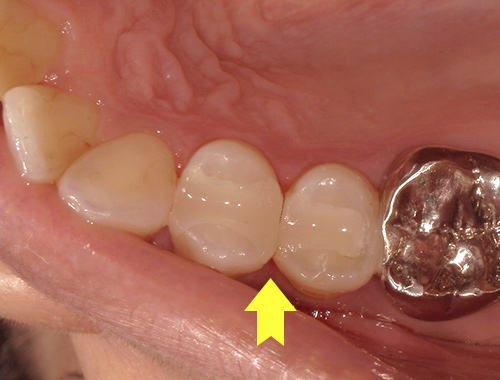

保険の詰め物から

白くて強度の強いジルコニアインレー(自費治療)に変更

保険診療で使用されていた金属の詰め物(いわゆる銀歯)を、白くて自然な見た目のセラミック(ジルコニア)に変更した症例です。金属の詰め物は強度に優れている一方、笑ったときや口を開けたときに目立ちやすく、長い年月が経つと金属成分が溶け出して歯ぐきが黒ずんで見えることがあります。

それに対し、セラミックの詰め物は見た目がとても自然で、天然歯とほとんど見分けがつかない仕上がりが可能です。金属を一切使用しないため、金属アレルギーの心配がなく、身体にも優しい素材です。

今回使用したジルコニアは、セラミックの中でも特に強度に優れており、歯を薄く削って作製できるという利点があります。一方で、オールセラミックに比べると透明感はやや出にくい素材です。患者さまから「なるべく歯を削らず、強度も確保したい」とのご要望があったため、このジルコニア素材を選択しました。精密に作製されるため適合性にも優れており、しっかりとフィットして虫歯の再発を防ぐ効果も期待できます。

写真では、治療前後の違いをご覧いただけます。黄色い矢印の部分が、実際にセラミックに置き換えた箇所です。治療後は口元の印象が明るくなり、患者さまにも大変ご満足いただけました。

治療期間通院3回(むし歯治療、型取り、セット)、約2週間程度

費用目安税込77,000円×2